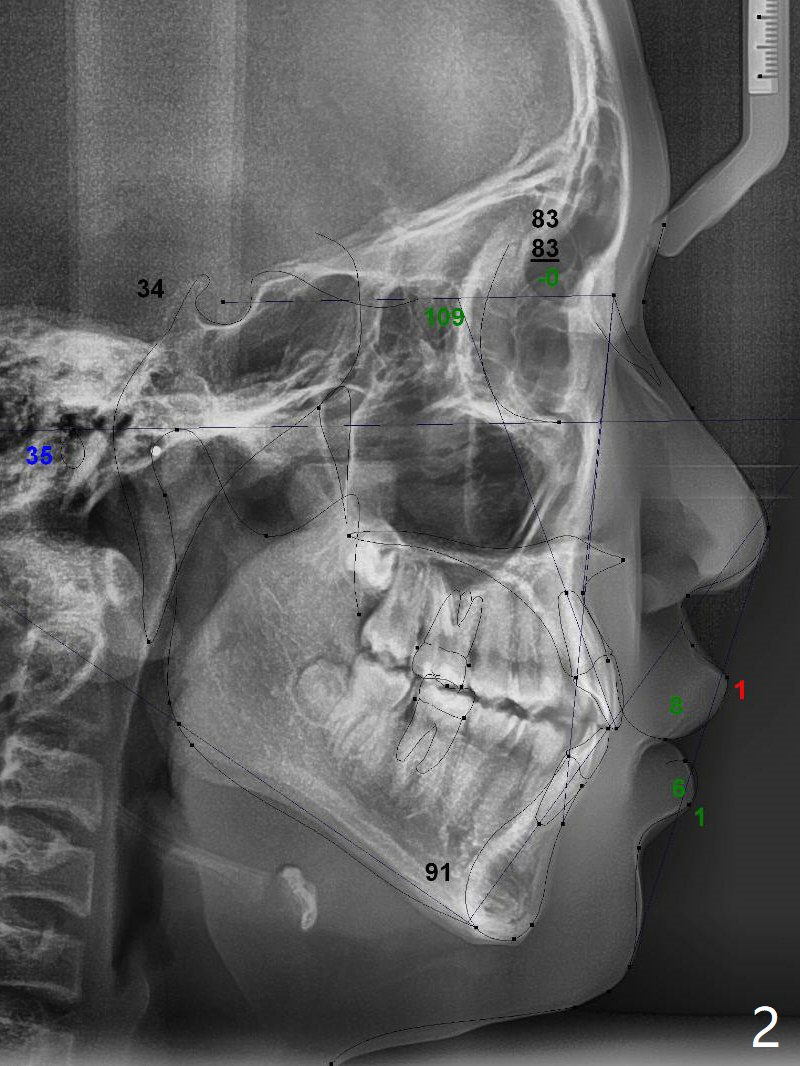

Preop cephalometric tracing shows normal skeletal relationship (Fig.1,2). The upper dental midline deviates to the right (Fig.3). To control root torque, UR1,3 bracketing is intentionally placed off (Fig.4,5, as compared to Fig.6). Take PA for UR1/3 next visit. In fact PA has not been taken. The patient has complained of UR1 turning (mesial incisal edge elongation due to bracket off placement) since the 1st appointment post banding. On the 3rd appointment (2 months 12 days post banding with 18 ss wire), the mesial incisal edge of UR1 and the distal incisal edge of UR3 are trimmed; 18 wires are reused with addition of an open coil spring between UR1-3 (Fig.7). Extra diastemata have appeared mesial and distal to UL1 (Fig.8 *), creating room to correct the upper dental midline shifting. PA is taken 5 months post banding (Fig.9). The roots of neighboring teeth are parallel with new bone formation behind. The mesiodistal space is similar to that of the tooth #10 following consolidation of diastemata on the left. More space is gained 12 months post banding (Fig.10).